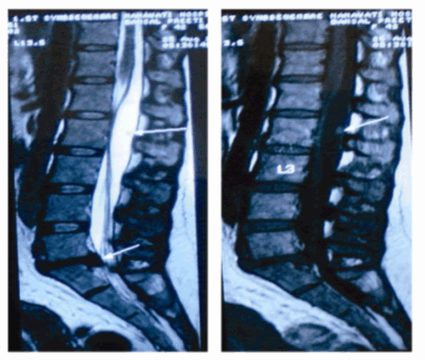

An MRI was done, that showed diffuse disc bulge at L5-S1 level with an inferiorly migrated central extrusion causing severe compression of the thecal sac (Figure 1, 2). It also revealed an intradural, extramedullary, cystic space occupying lesion with an internal solid-cystic nodule, extending from L1 to L2-3 causing compression and anterior displacement of filum and cauda equina (Figure 1). The lesion showed signal intensities similar to those of CSF on T1, T2 and FLAIR images. There was no enhancement noted after administration of contrast in the MR scans. The imaging features were suggestive of a benign cyst with possibilities of a cysticercosis or an arachnoid cyst.

Figure 1: T2 and T1 sagittal MRI films showing intradural, extramedullary cystic, space occupying lesion with an internal solid-cystic nodule, extending from L1 to L2-3 causing compression and anterior displacement of filum and cauda equina with signal intensities similar to those of CSF.